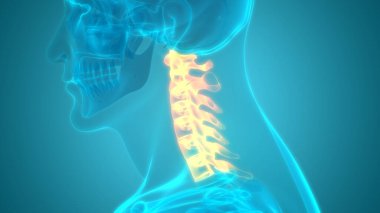

İnsan İskeleti Omurgası Servikal Omurga Anatomisi 3D İllüstrasyon

İnsanTıbbiparmakBoyunomurgaKalçaRADIUSsakralGöğüs kemiğiskapulaLeğen kemiğitorasikçene kemiğiparietallombersakrumTibiaUyluk kemiğiKöprücük kemiğisokumupazı kemiğidirsek kemiğioksipitaldiz kapağıkemikler3d oluşturmaGöğüs kafesiüst ekstremiteOmurga SütunuAyak bileği Ağrısıbel kemiğiayak kemikleriiskelet anatomisidiz eklem ağrısıservikal bölgeclavicle bonewrist carpalscervical vertebrae anatomyBenzer İçerikler